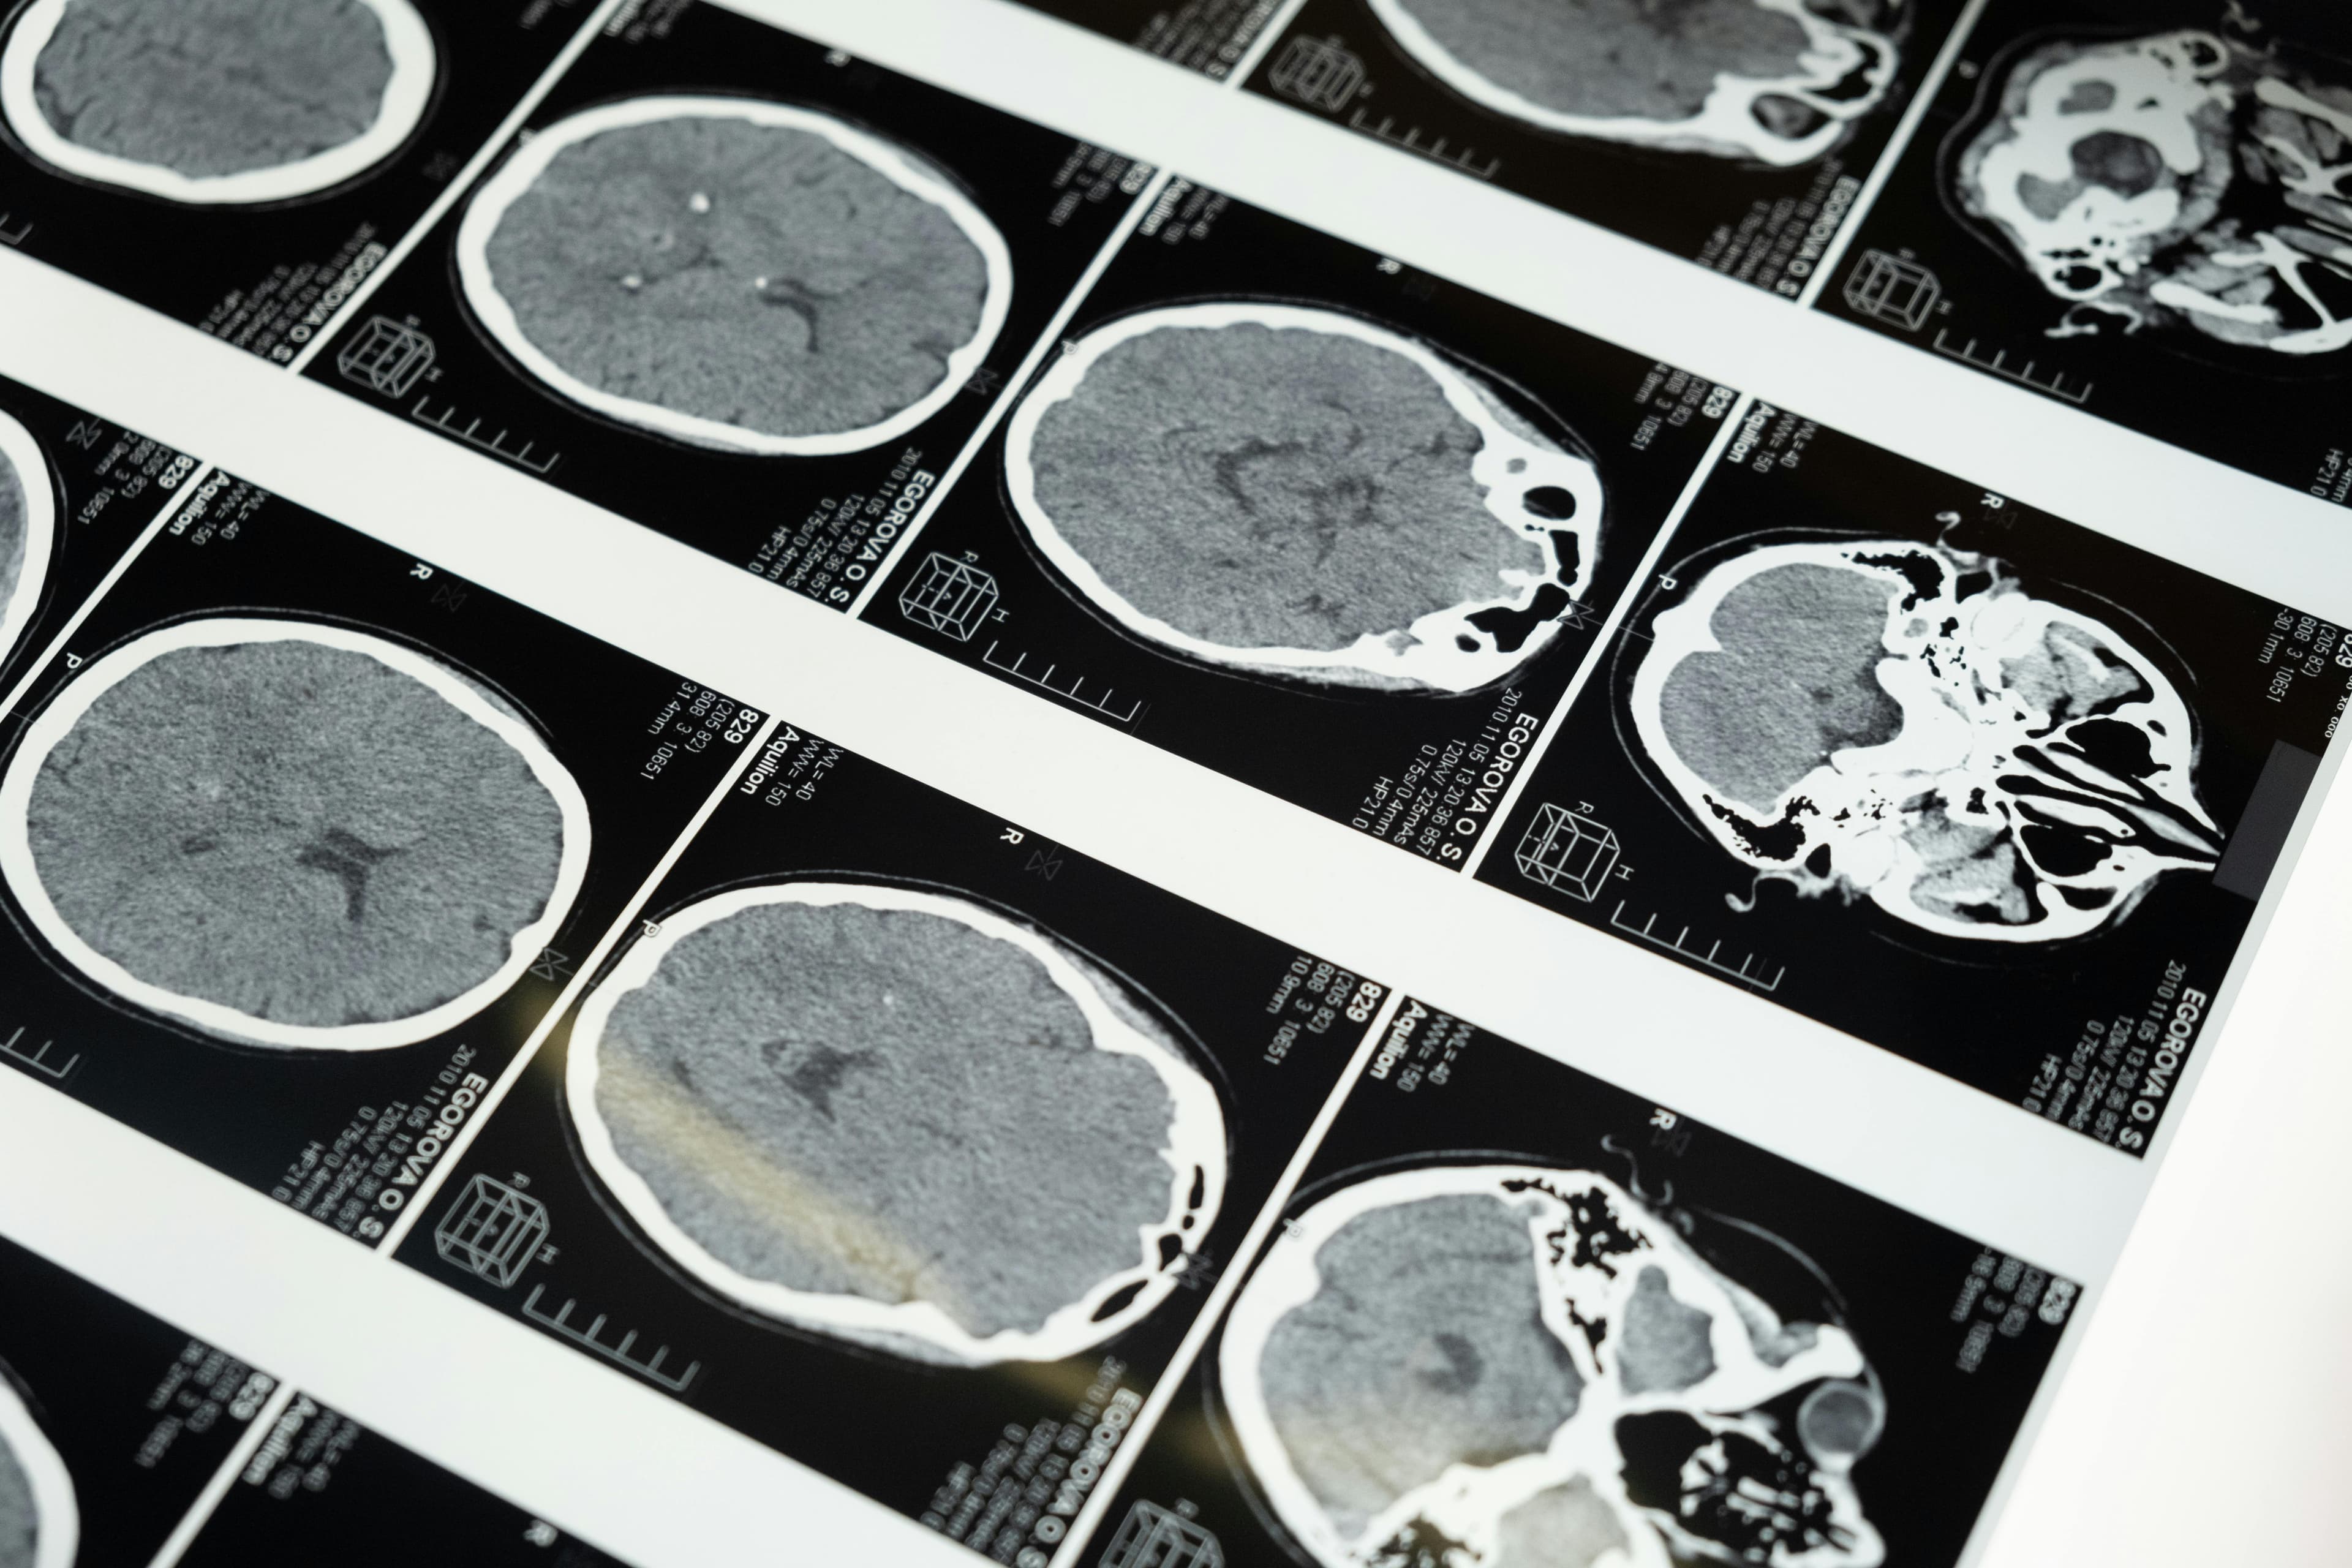

Understanding the TBI Epidemic

Traumatic brain injuries (TBIs) have become a silent public health crisis, affecting lives in unexpected ways. In the United States, TBI-related emergency room visits increased by 53% between 2006 and 2014, representing millions of altered lives.

These injuries range widely in severity and impact. Some patients, like my friend, suffer from mood changes, memory difficulties, and inability to do tasks like read or watch TV. Others suffer from devastating emotional effects like depression or uncontrollable anger.

From mild concussions to severe trauma, TBIs can have long-lasting cognitive, emotional, and physical effects that take months or even years to resolve.